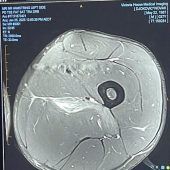

Novak Djokovic hat nach seiner Aufgabe bei den Australian Open in den sozialen Medien ein Foto seiner Verletzung geteilt. „Ich dachte, ich lasse dies hier für alle ‚Experten‘ von Sportverletzungen“, schrieb der Serbe zu einem MRT-Bild. Djokovic... zum Artikel